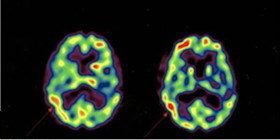

這種行為和感受其實可以用科學解釋。首先看看人在普通祈禱時腦部的活動,University of Pennsylvania醫學院的Andrew Newberg教授的研究顯示:當人祈禱時,他的前腦(prefrontal cortex)十分活躍(呈紅色),圖一腦掃描上段是前腦部分,左邊是祈禱前,右邊是祈禱時掃描,意思是祈禱幫助人鍛鍊思想和邏輯,而腦側的 Parietal lobe也呈現紅色,代表他對周邊環境的感覺也加深,換句話說,祈禱會使人的思想更深入敏銳,更能控制感受和言語。

圖一:祈禱前(左)後(右)的腦部掃描,紅色表示活躍之處。